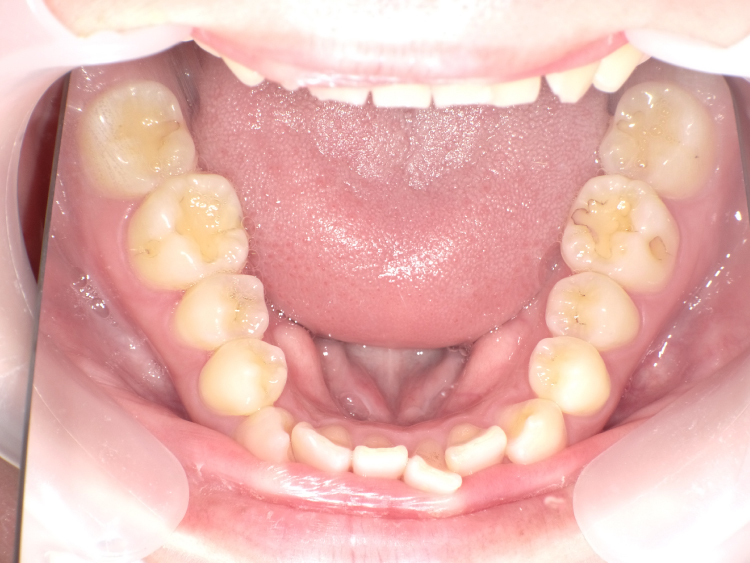

症例3

治療前

治療後

| 主訴 | 上下前歯全体の歯並びが気になる |

|---|---|

| 治療 期間 |

約6ヶ月 |

| 治療費 | 330,000円(税込)/調整費用別途 |

| 治療 内容 |

上下の前歯部にワイヤーを着けて進めていく、プチ矯正で施術。 |

| 治療の リスク |

固定の装置をつけないと後戻りしてしまう。 |